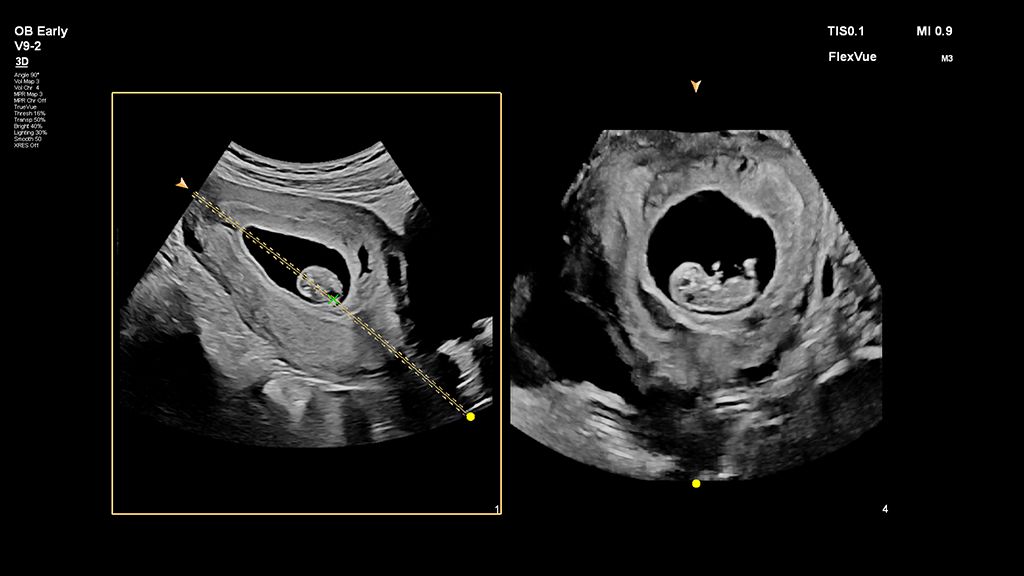

Demonstrated results using FlexVue

It (FlexVue) takes all of the complications out of MPR and manipulation of a surface-rendered volume. By deploying a straight line or a curved trace or continuous trace, we can take a curved image, flatten it out and make it a single planar image.